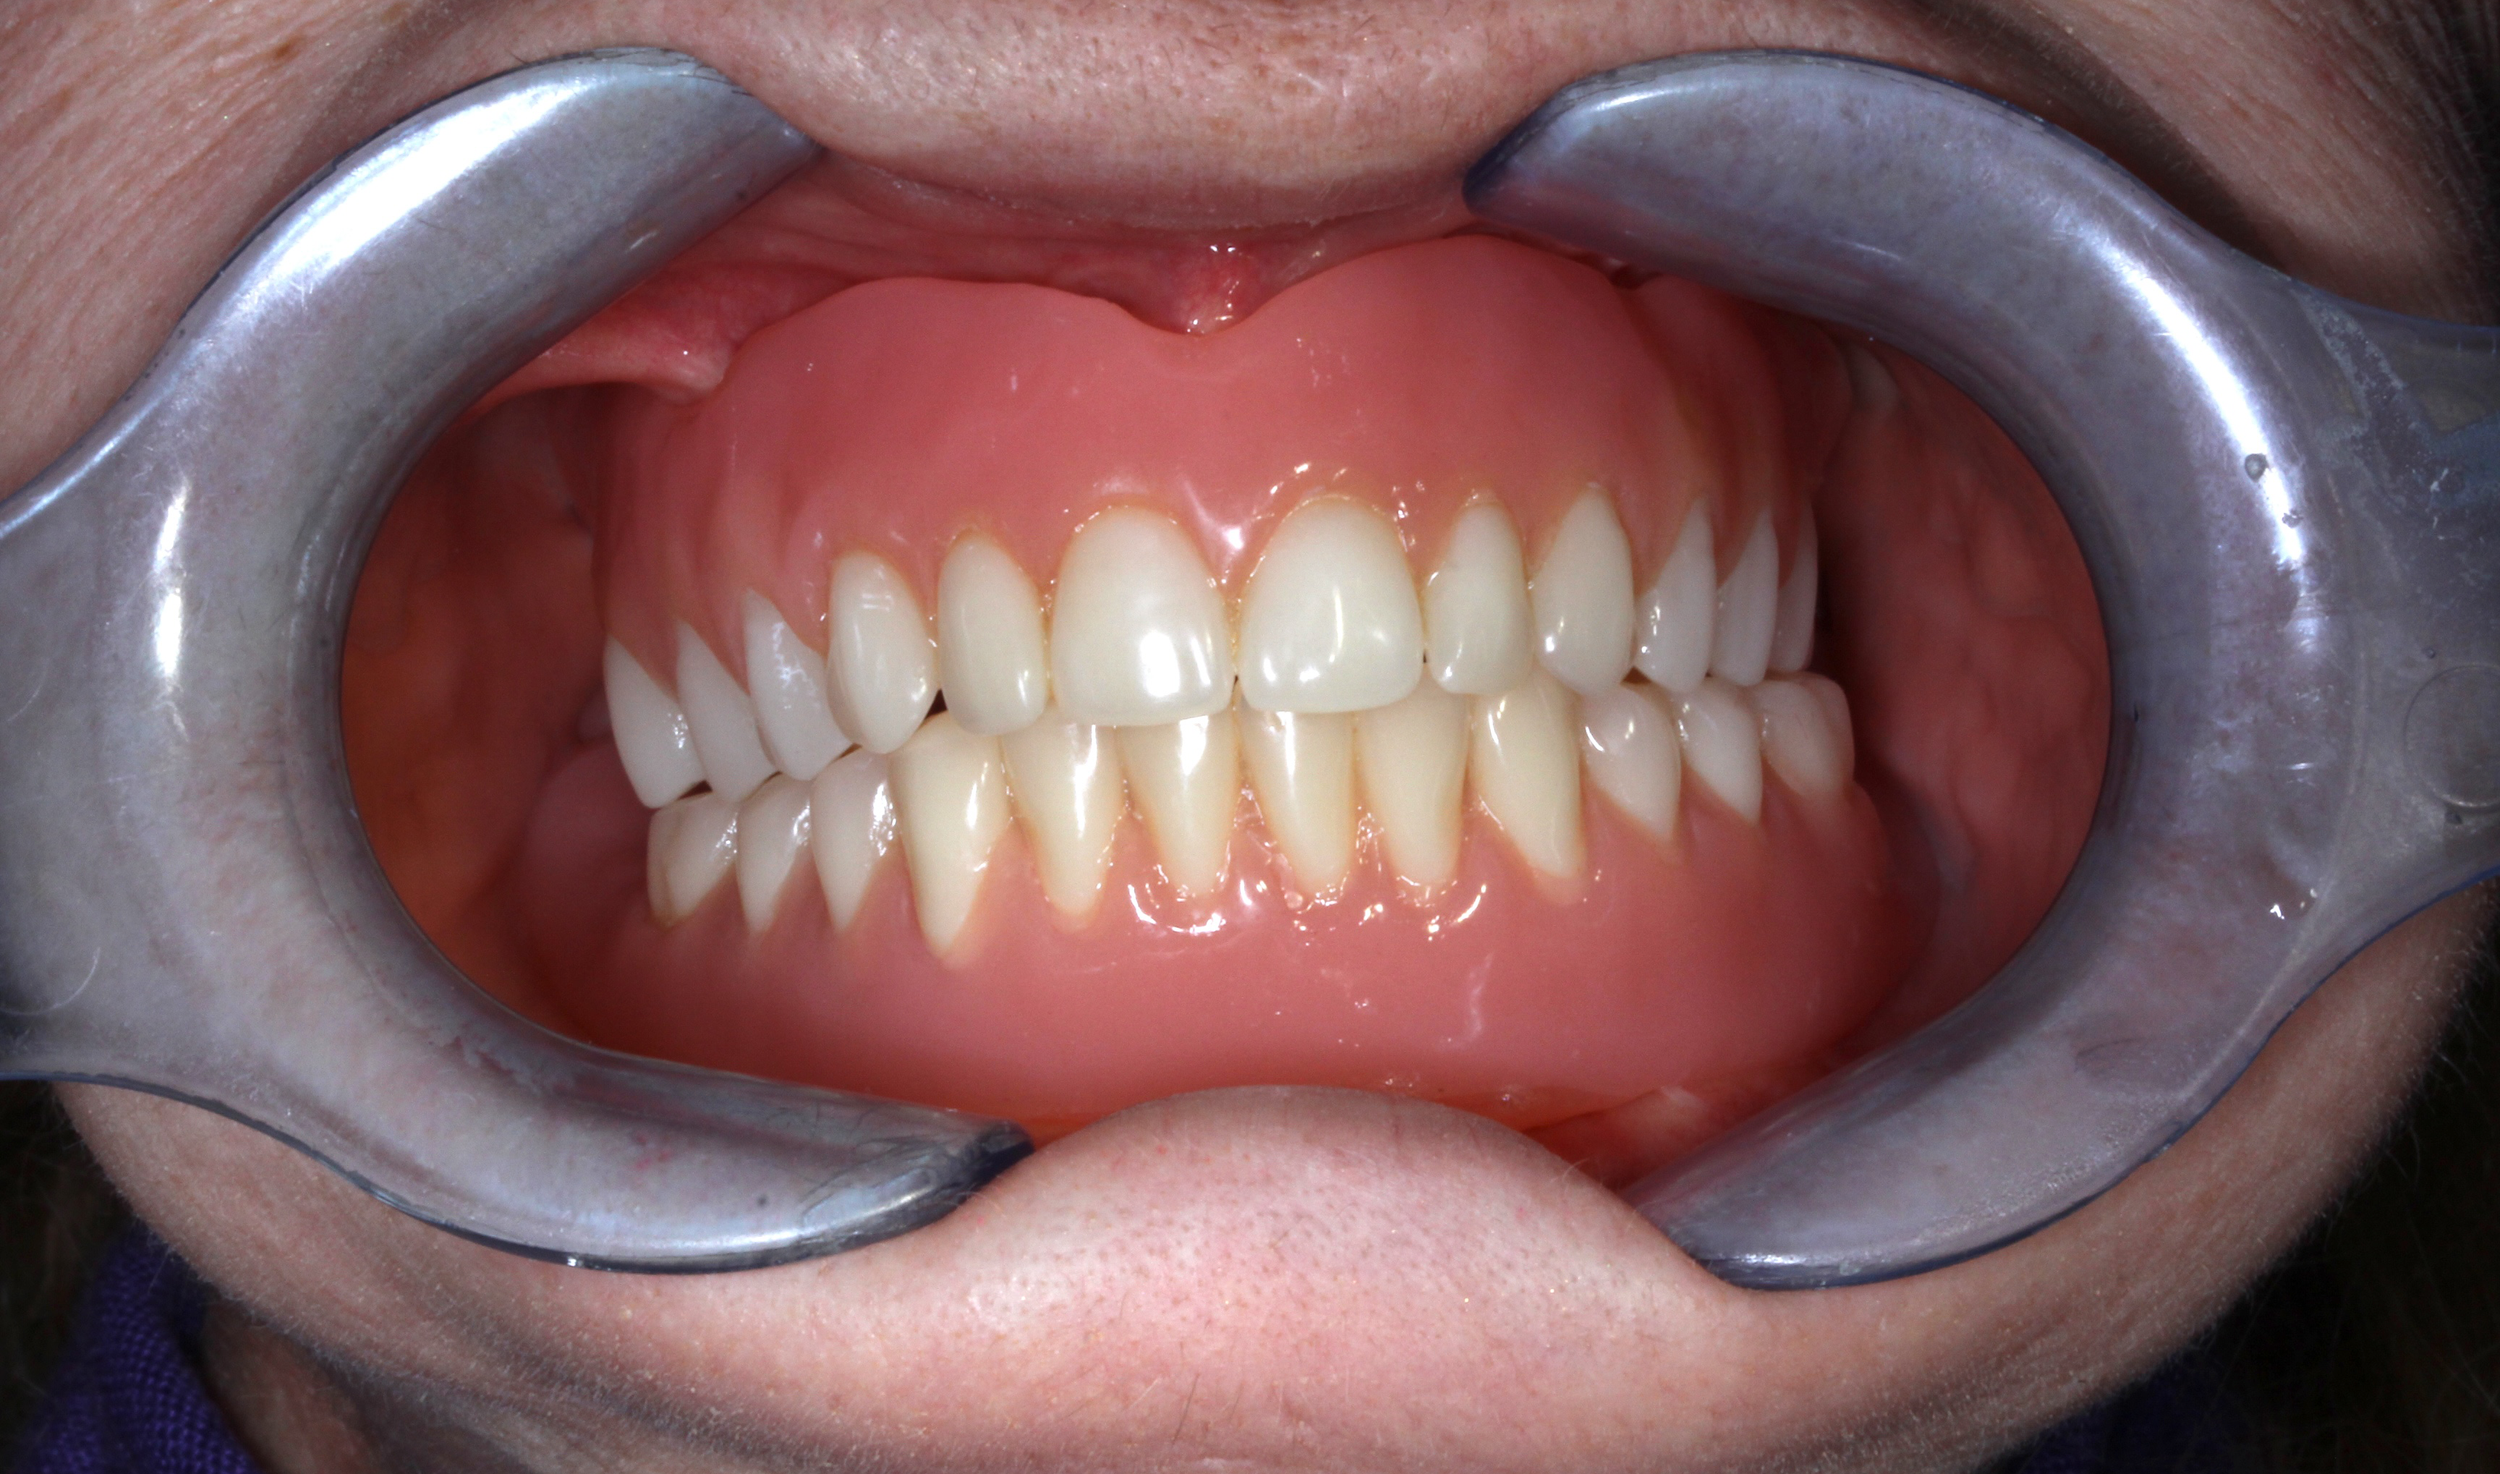

Riabilitazioni complete nei pazienti totalmente edentuli

Quando invece il paziente ha perso tutti i denti, progettiamo una riabilitazione completa supportata da impianti dentali. Grazie a tecniche avanzate e pianificazioni personalizzate, è possibile ripristinare estetica, funzione masticatoria e comfort attraverso soluzioni fisse stabilmente ancorate all’osso, restituendo un sorriso nuovo e sicuro anche nelle condizioni cliniche più complesse.

Caso 5

A causa di vari problemi di salute, la paziente si trova in una situazione di edentulia completa in entrambe le arcate. Le attuali protesi mobili sono per lei fonte di forte insicurezza a causa della loro mobilità. Nonostante la scarsità di osso mascellare e la presenza di viti di osteosintesi nella mandibola si procede con una riabilitazione fissa su entrambe le arcate combinando impianti tradizionali (mandibola) con impianti iuta-gengivali, nella mascella.

DOPO